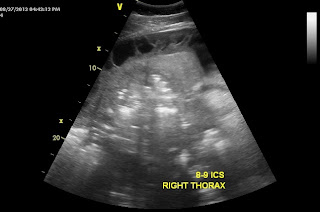

When I examined the horse, the gelding was in distress! His heart rate was 80 bpm, respiratory rate was 60-70 bpm (shallow) and his body temperature was 102 degrees. Auscultation of the thorax noted lung sounds (sound of air moving in and out of lungs) on both sides of the horse only ABOVE the level of the shoulder but lung sounds were absent or muffled below the level of the shoulder. Suspecting pleuropneumonia, I performed a trans-thoracic ultrasound exam. A significant amount of fluid was noted in the pleural space along with large fibrin tags and multiple abscesses! ( Figure 1-3).

In the video clips below, the fibrin tags can be seen "floating" in the excessive fluid within the pleural space. In addition, the fluid appears as "cellular" suggesting a heavy component of fibrin and purulent debris (pus).

In Figure 2-3, large abscesses are noted adjacent to the body wall. Ultimately, these abscess would need to be exteriorized through a rib resection in order for the horse to completely heal. Unfortunately, the ultrasound findings combined with the severe physical distress were very poor prognostic indicators and the owner elected humane euthanasia! There was near zero chance that this horse could have been saved regardless of the medical and surgical intervention provided!